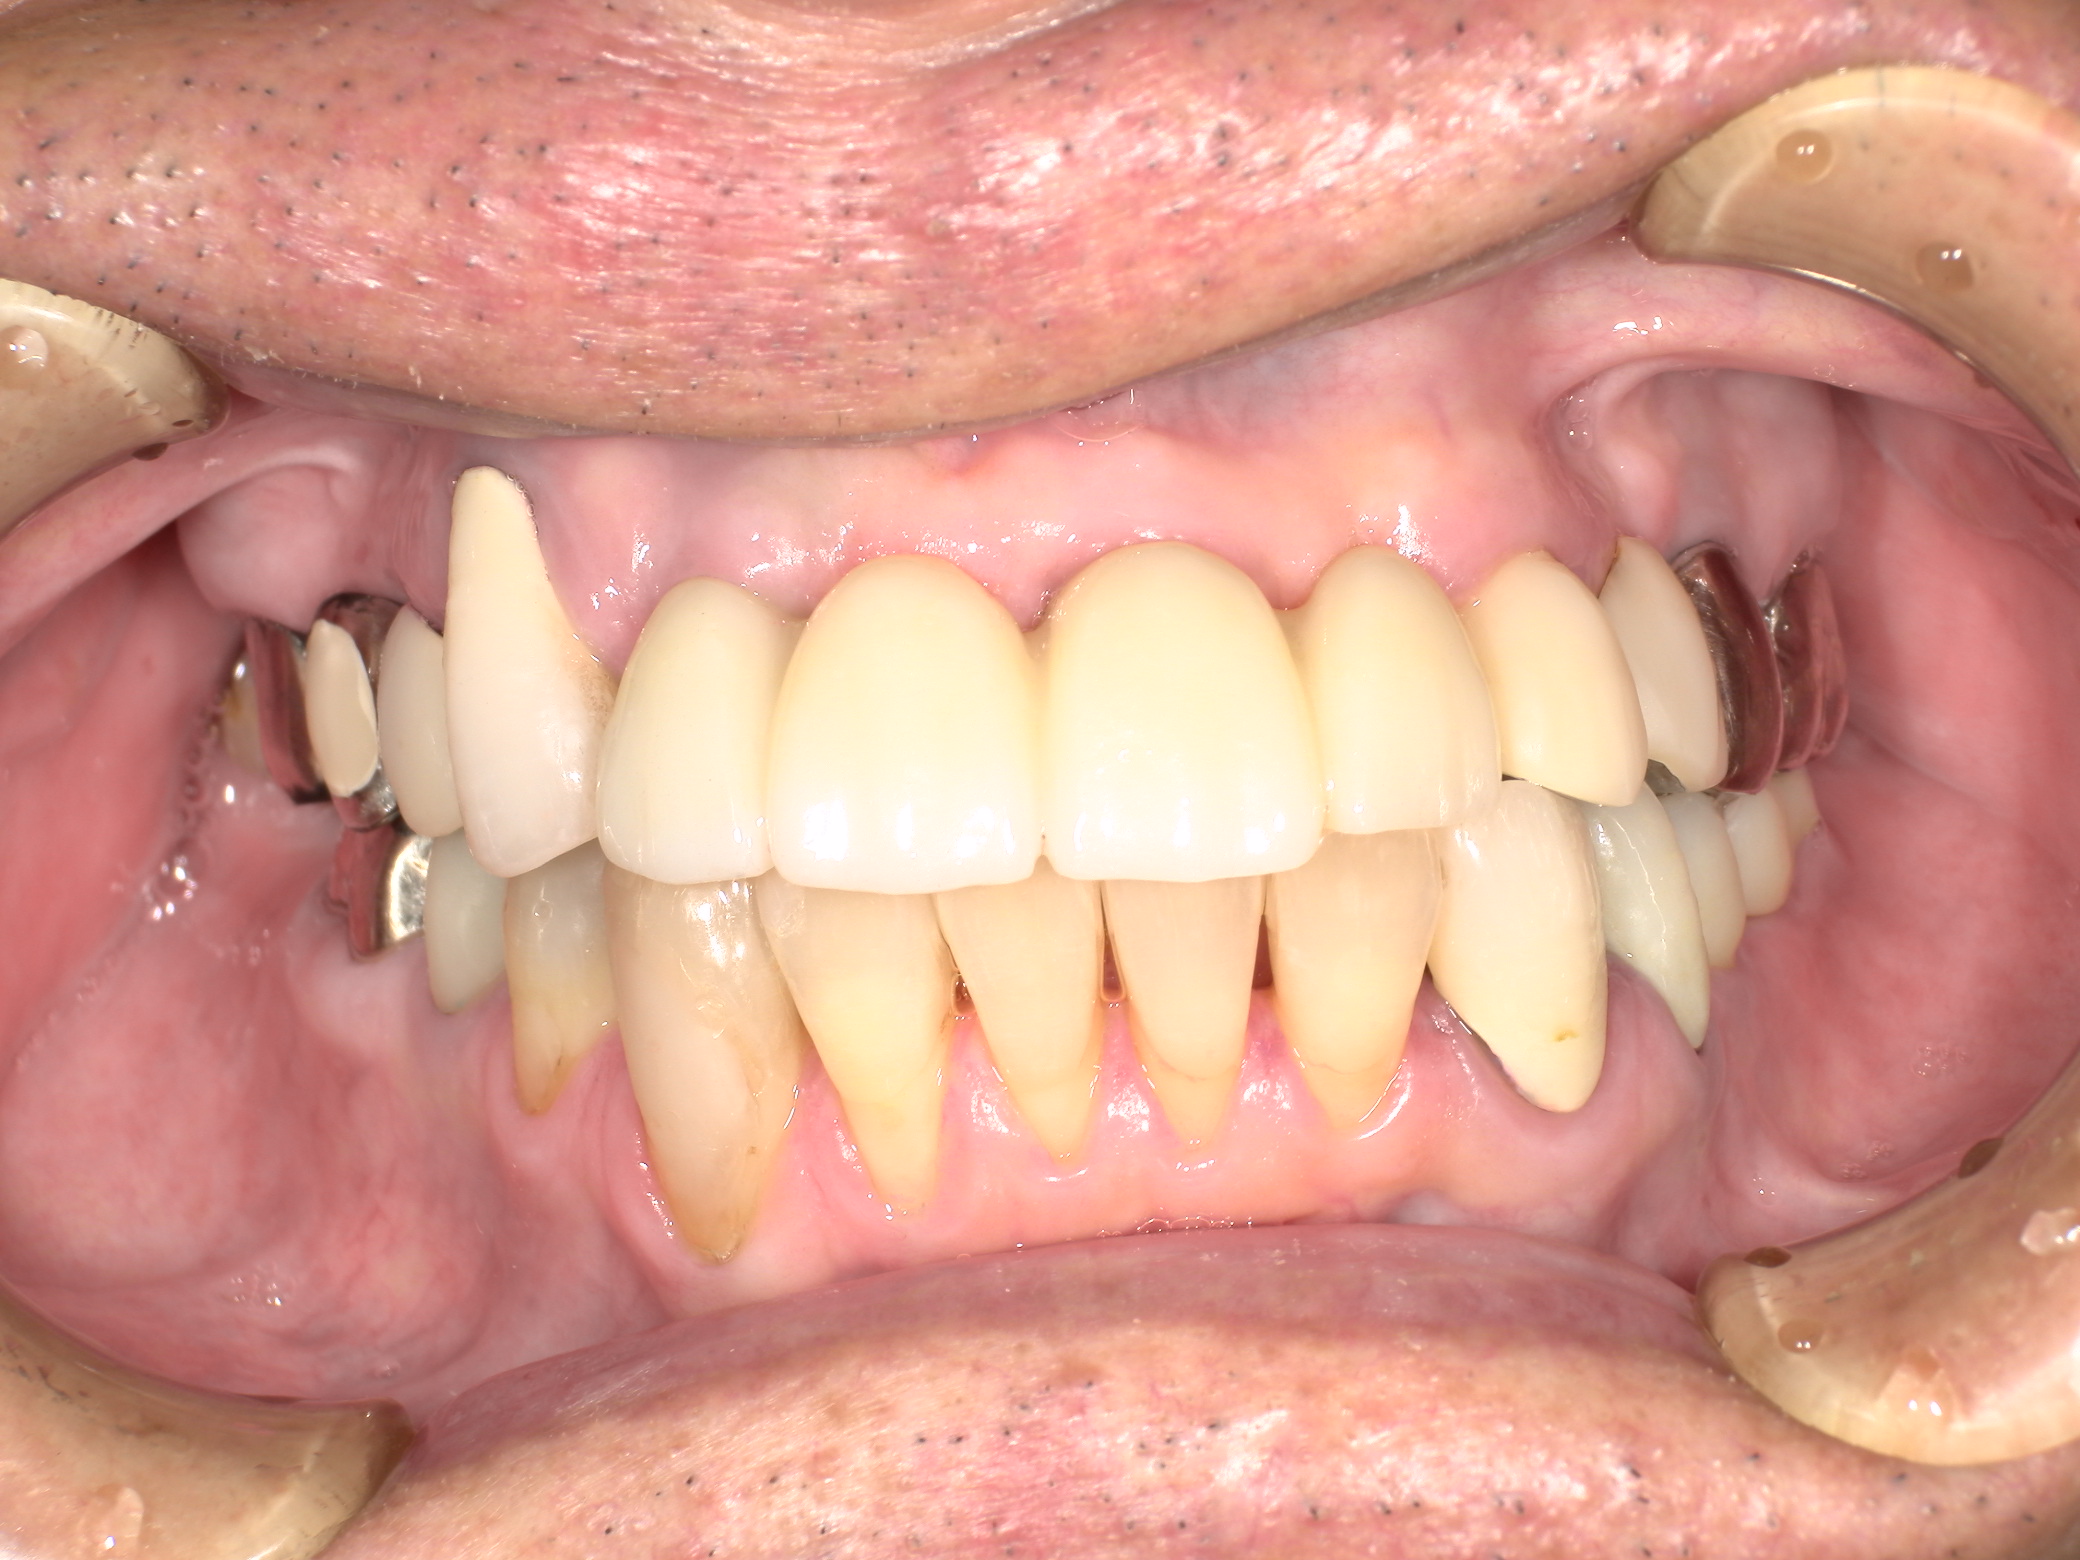

インプラント施術前

下あごの奥歯がなく、食いしばりが強いため前歯もすり減ってしまいました。

インプラント施術後

インプラントを6本埋入してかみ合わせも適当な高さに改善、前歯もセラミックをかぶせて見た目も改善しました。